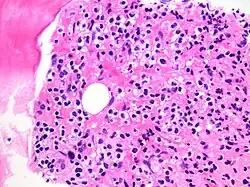

Hairy cell leukemia infiltrating bone marrow, an example of malignant infiltration

Malignant infiltration involves cancerous cells invading surrounding healthy tissues by breaching normal cellular boundaries, which allows tumors to grow locally and facilitates metastasis to distant organs. This is especially relevant for cancers that cross the blood-brain barrier and cause secondary brain tumors.[3]